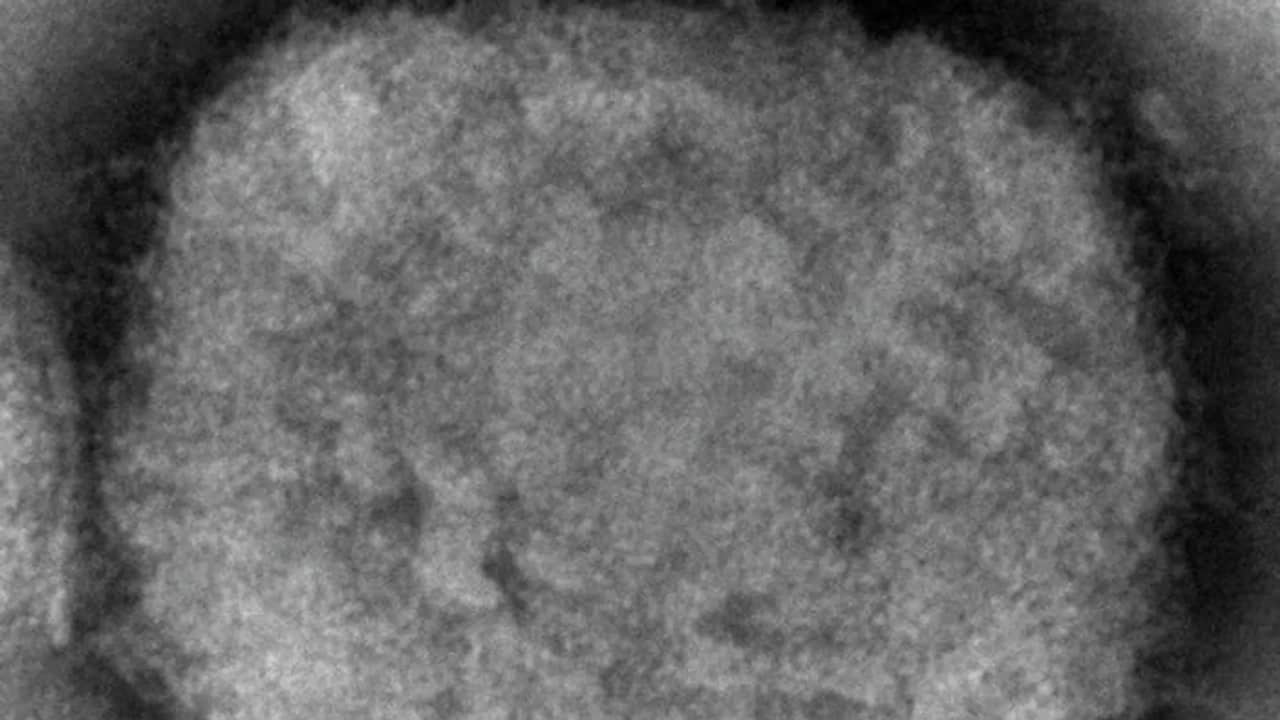

7NEWS.az xəbər verir ki, pandemiyaya çevrilmə ehtimalı olmayan və yayılma sürətinin "Covid-19” ilə eyniləşdirilməməsi lazım olduğunu vurğulayan meymunçiçəyi virusu Avropanın başqa bir ölkəsində də görülüb. Almaniyada yoluxma üçün 21 günlük karantin gündəmdədir.